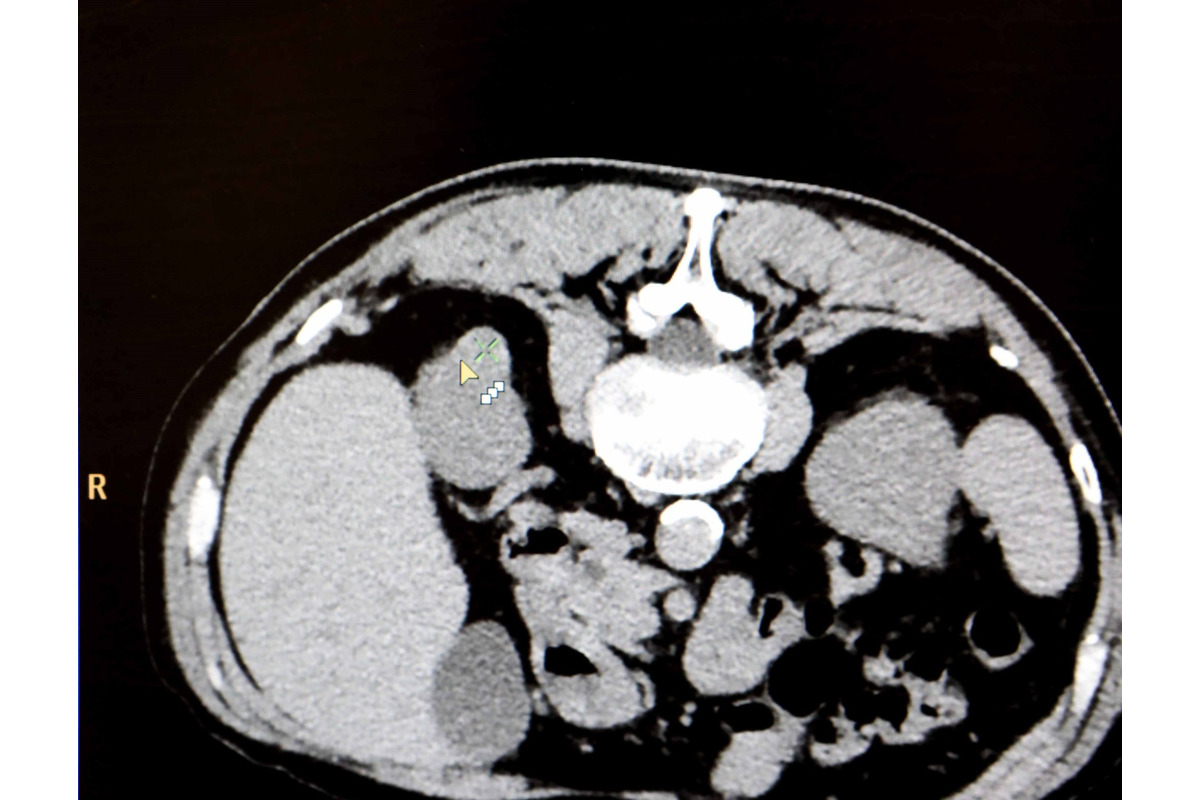

FOTO: Košická univerzitná nemocnica zaviedla pokrokovú liečbu tumorov

FOTO: Košická univerzitná nemocnica zaviedla pokrokovú liečbu tumorov, foto 5

Zdroj: UNLP